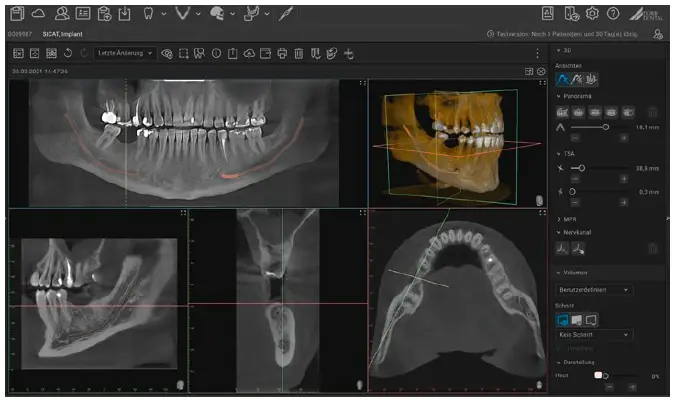

VistaSoft 3D

The package comes with a full 2D and 3D X-ray licence for VistaSoft, which allows you to view 2D and 3D image data and perform diagnoses – even without your own dedicated CBCT device

Website